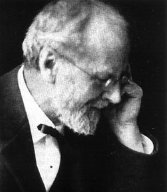

뇌엽 절제술은 1930년대에 시작된 정신 질환 치료를 위한 외과적 수술로, 1935년 안토니오 에가스 모니즈에 의해 처음 시행되었다. 이 시술은 전두엽의 특정 부위를 절제하여 정신 질환을 치료하려는 시도로, 말라리아 요법, 인슐린 쇼크 요법 등과 함께 당시의 급진적인 신체 치료법 중 하나였다. 뇌엽 절제술은 환자의 증상을 완화하는 데 기여했지만, 자발성, 책임감, 자기 인식 등을 감소시키고 인지 능력 저하를 야기하여 비판을 받았다. 1940년대부터 뇌엽 절제술의 위험성과 비윤리성에 대한 비판이 제기되었으며, 소련을 비롯한 여러 국가에서 금지되었다. 대한민국에서는 1942년 처음 시행되었으며, 일본 정신 신경 학회에서 정신 외과를 부정하는 결의를 통해 폐지되었다.

뇌엽 절제술은 1930년대 초반부터 정신 질환과 그 치료법에 대한 관심이 높아지면서, 1935년 포르투갈의 신경과 의사이자 정신외과의인 안토니오 에가스 모니즈에 의해 처음으로 시행되었다.[155] 모니즈는 외과적 뇌 수술을 통해 정신 질환 치료의 새로운 가능성을 열 수 있을 것이라 기대했다.[155]